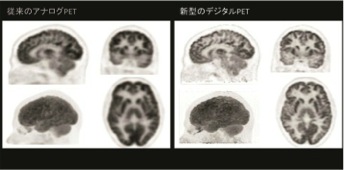

現在PET/CT装置に求められる3要素である分解能(空間的/時間的)、感度、定量性について全て2倍超(従来比)にスペックを改善し、画質/投与量/収集時間に妥協することなく臨床に求められるニーズに対してより戦略的なPET/CT検査を可能とし、近い将来の応用が待たれる新規PET製剤の基礎・臨床研究においてもインパクトのある貢献が期待される。

3.2倍超の感度、空間分解能、定量性向上による臨床への期待

デジタル

Si−PM検出器の搭載でTime-of-Flight方式の時間分解能は345ピコ秒まで短縮され、PETに必要な感度、空間分解能、定量性ともに(従来比)2倍超のスペックアップを達成している。特にPET画像は画質のみならず、SUV(Standard Uptake Value:標準取り込み値)に代表される定量値の精度が求められる。ダイナミックレンジの改善により従来PETでのSUV値に比べて精度の高い定量を追及した。今後、デジタルPET/CTでのSUV値の検証やデータの蓄積によって、悪性度の判定、治療方針の決定や治療効果判定のみならず未知の病態解明などへの貢献が期待される。